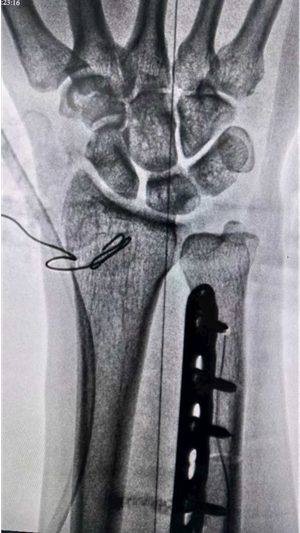

X线片示:尺骨正向变异,月骨可见低密度囊性透亮影。

尺骨短缩截骨,避免尺月撞击